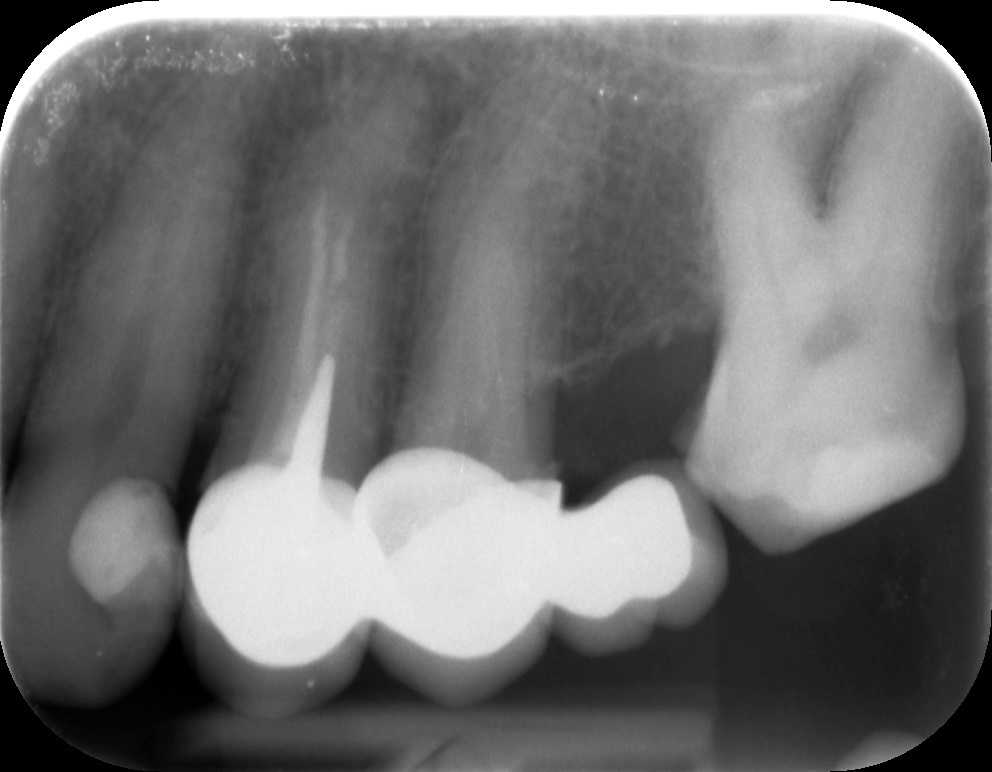

Dr. Molnár Katalin páciense a bal felső fogaknál jelentkező tompa fájdalomra panaszkodva érkezett fogászatunkra. A panorámaröntgent követően készítettünk kisfelvételt is az érintett oldalról.

A képen látható, hogy a bal felső négyes fog a híd alatt csappal van megerősítve, és a gyökértömés a csatornákban nem ér végig. Ennek következtében a gyökércsúcs körül gyulladás alakult ki. Nyilvánvalóvá vált, hogy a híd levételére, a csap és a gyökértömés mikroszkóppal történő eltávolítására lesz szükség.